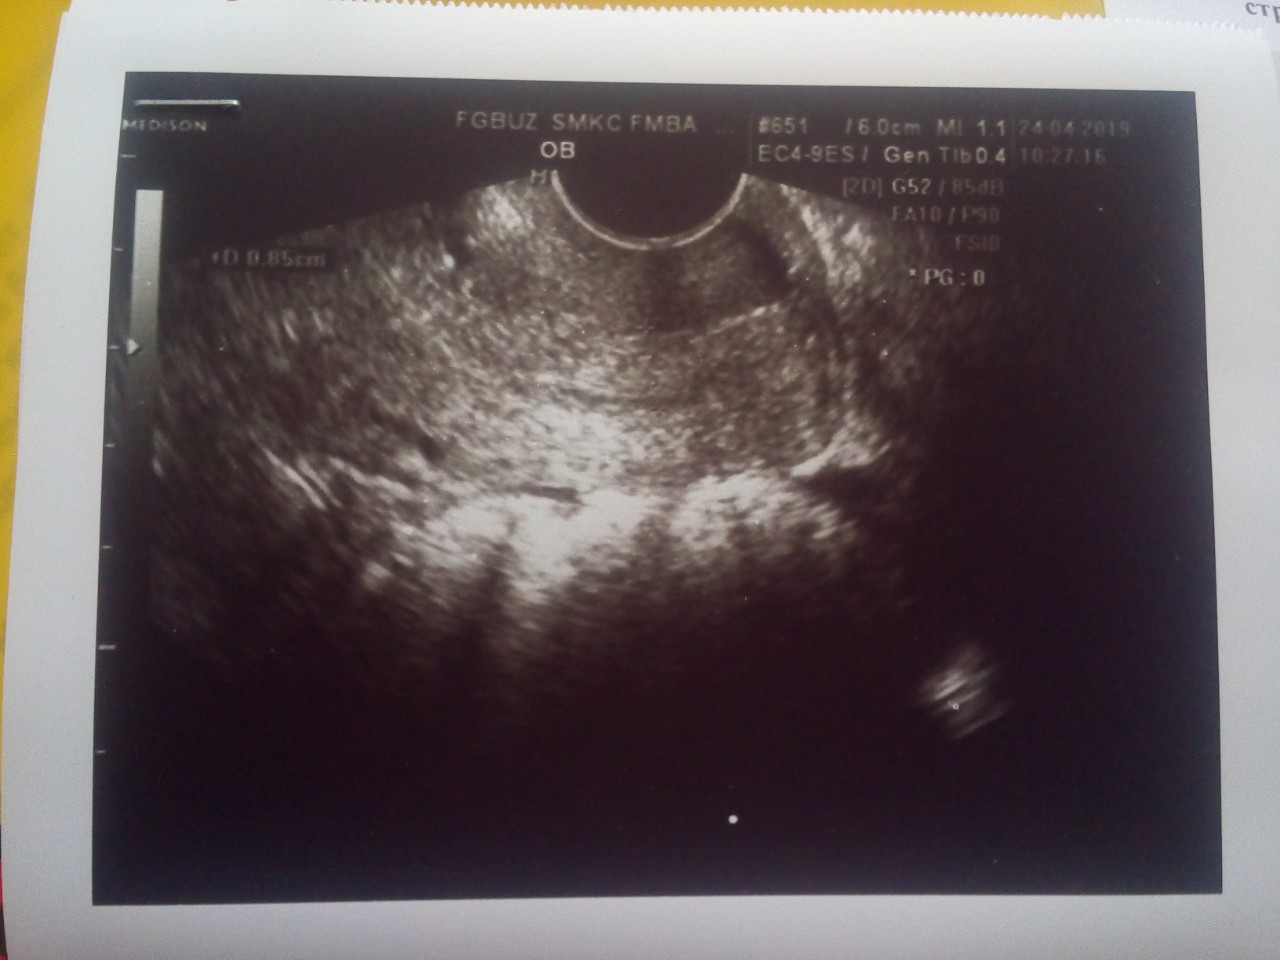

Здравствуйте, уже около года беспокоит кровянистые выделения во время овуляции (вместе со слизью как яичный белок выходит достаточное количество кровяных прожилок, чтобы одеть прокладку с двумя каплями), продолжаются около 2 дней +-. Сопровождаются слабой, но неприятной тупой болью внизу живота. Обращалась к врачу, шейка матки чистая, мазок тоже, она ставила аднексит, отправляла на узи (4мес. Назад) всё было в норме. Сегодня прошла узи уже платно, по собственной инициативе на 7 день цикла. Мне сказали сама матка чистая, яичники в норме, но вот цервикальный канал сильно увеличен 8-10мм и в средней зоне наблюдается утолщение с образованием повышенной эхогенности без четких контуров, предположила полип (со знаком вопроса), но сама же вслух сказала, что нечеткие контуры - это скорее всего не полип. Фото результата узи прилагаю: пожалуйста, подскажите, нечеткие контуры это рак и готовится к худшему? И какое еще уточняющее исследование лучше пройти чтобы подтвердить или исключить?